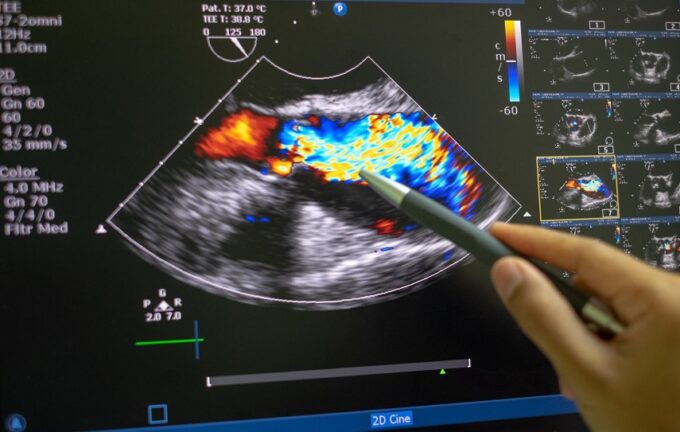

Eco transesofageo: il test che rivoluziona la diagnostica cardiaca

L’eco transesofageo sta rapidamente diventando un punto di riferimento nella diagnostica cardiaca. Se ti sei mai chiesto cos’è questo esame, come funziona e perché...